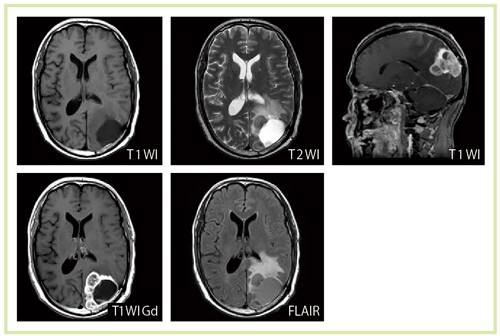

図3 脳腫瘍症例における種々のシーケンスによる画像(Titan 3T)

3T MRIによる心臓は,susceptibility artifactの影響やSAR(specific absorption rate)の制約のために,従来は撮像が困難な領域であった。しかし,Titan 3Tでは非常に明瞭な画像が得られている(図5〜8)。